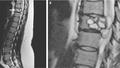

Dijon : une femme vivait avec un ver dans une vertèbre

Une femme de 35 ans s’est présentée à l’hôpital suite à des chutes répétées et des sensations de chocs électriques dans les jambes. Le coupable ? Un ver parasite qui comprimait sa moelle épinière.